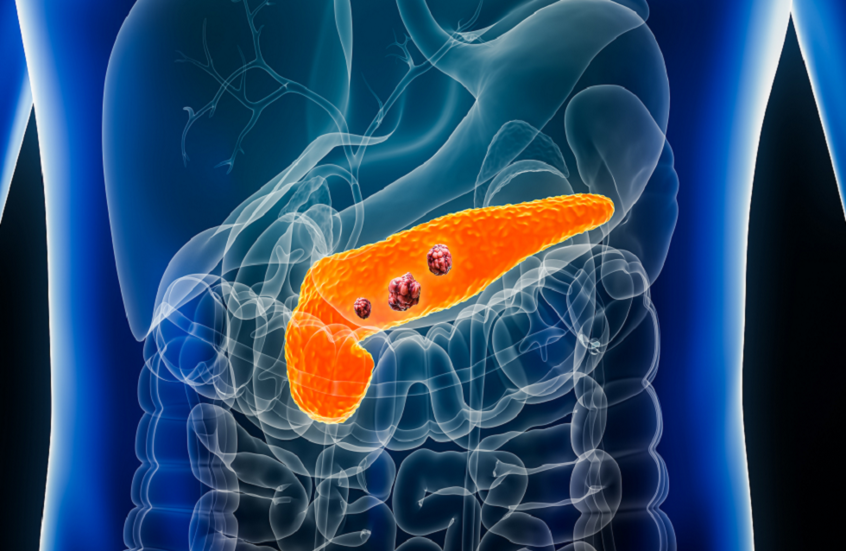

فحص دم جديد قد ينقذ آلاف الأرواح من سرطان البنكرياس

طور علماء من جامعة بنسلفانيا وعيادة مايو فحص دم مبتكر يمكن أن يساعد في الكشف المبكر عن سرطان البنكرياس، أحد أخطر أنواع السرطان وأصعبها علاجا.

ويعتمد الفحص الجديد على دمج أربعة مؤشرات حيوية في اختبار واحد: المؤشرين المعروفين CA19-9 وTHBS2، والبروتينين الجديدين ANPEP وPIGR، اللذين وُجدت مستوياتهما أعلى لدى المصابين بسرطان البنكرياس في مراحله المبكرة مقارنة بالمتطوعين الأصحاء.

وعند دمج المؤشرات الأربعة، بلغ معدل دقة التشخيص 92%، مع نتائج إيجابية خاطئة بنسبة 5% فقط لدى الأشخاص غير المصابين، وكشف نحو 8% من الحالات في مراحل مبكرة للمرض.

ويأمل الباحثون أن يُستخدم الاختبار لفحص الأشخاص الأكثر عرضة للإصابة، مثل من لديهم تاريخ عائلي للمرض أو عوامل وراثية أو تكيسات في البنكرياس أو التهاب البنكرياس المزمن.

ويشير الدكتور كينيث زاريت، الباحث الرئيسي في الدراسة، إلى أن إضافة المؤشرين الجديدين حسّنت بشكل ملحوظ قدرة الاختبار على كشف السرطان مبكرا، كما ساعدت في التمييز بين السرطان والحالات غير السرطانية مثل التهاب البنكرياس، وهو ما كان يمثل تحديا للاختبارات السابقة.

ورغم النتائج المبشرة، يحتاج الاختبار إلى سنوات من التجارب قبل اعتماده للاستخدام العام.

وفي الوقت الحالي، يظل سرطان البنكرياس مرضا صعب العلاج وغير قابل للشفاء غالبا، إذ يؤدي إلى فشل الأعضاء نتيجة غزو الأعضاء المجاورة وانسداد القنوات الصفراوية والمعوية، وانتشار السرطان عبر الدم والجهاز اللمفاوي.

ويؤدي سرطان البنكرياس أيضا إلى اضطراب إفراز هرمونات البنكرياس مثل الأنسولين والغلوكاغون، ما قد يسبب مشاكل في مستويات السكر بالدم. وتشمل الأعراض الشائعة للمرض اليرقان وفقدان الشهية والوزن والتعب والغثيان أو القيء والإسهال أو الإمساك.

وأشارت دراسة سابقة إلى أن أكثر من نصف المرضى المصابين بالأنواع الأقل قابلية للشفاء من السرطان، بما في ذلك سرطان البنكرياس، يتوفون خلال عام من التشخيص.

وفي سياق متصل، نجح فريق بحثي إسباني مؤخرا في تطوير خطة علاجية "ثلاثية الفعالية" قلصت حجم خلايا سرطان البنكرياس، ما يمنح الأمل في تحسين نتائج العلاج مستقبلا.

نشرت الدراسة في المجلة الطبية AACR.